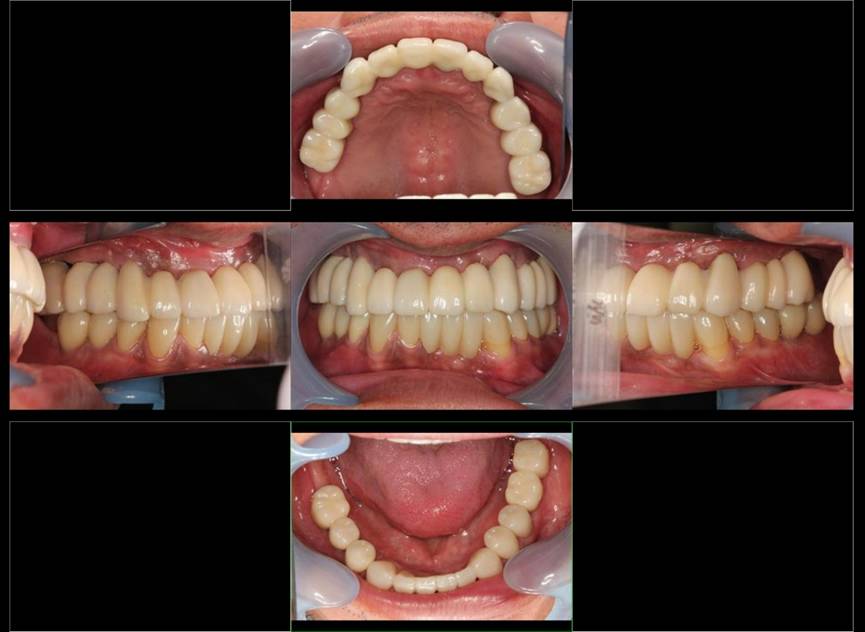

術後。上部構造はハイブリッドレジンです。しっかり嚙めるようになり喜んでいただきました。

上顎

下顎

上部構造装着後6年。ハイブリッドレジンを使用したため、少し艶がなくなってきました。上部構造の材料には金属、ハイブリッドレジン、セラミックなどがあります。セラミックはきれいですが欠けやすいため、最近はフルジルコニアを使っています。

上顎 少しすり減ってきました。

下顎。12か月に一度メインテナンスをしています。

インプラント装着後6年。順調に経過しています。12か月毎のメインテナンスをしています。